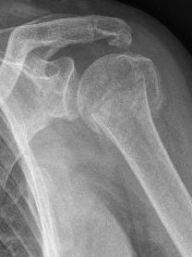

Proximaler Oberarmbruch7Proximaler Oberarmbruch8

Picture: In the above pictures, a slightly shifted subcapital humeral fracture was internally splinted using intramedullary nail. The left picture is a follow-up examination half a year after the accident and shows the complete healing of the fracture with correct position of the bone.